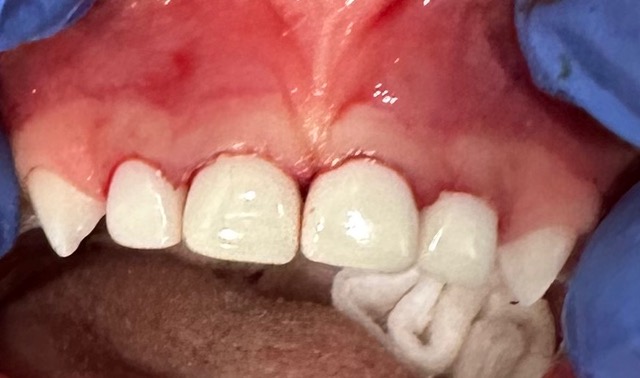

When a cavity is too large for a filling, a pediatric crown provides the strength and protection a tooth needs to stay healthy.

At Luce Tooth, we offer both stainless steel and beautiful tooth-colored zirconia crowns, giving each family the option that fits their child’s needs and smile.

Our gentle, evidence-based approach ensures your child stays comfortable while we restore the tooth to full function, durability, and confidence.